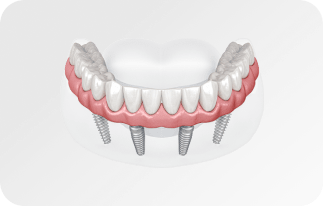

Зубы за 1 день за 5776р. в месяц

с пожизненной гарантией

По уникальной методике

БЕЗ отёков и надрезов

Установка

за 1 день